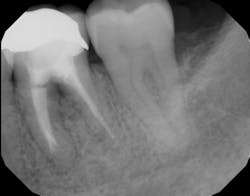

Figure 1: Molar with periodontal abscess due to furcation involvement

Figure 1a: Deep Class II furcation with an entrance smaller than the diameter of a curette tip

In other words, even experienced clinicians who access a root surface with flap surgery are sometimes limited in the amount of detoxification that can occur due to the depth of the defect and conventional instrumentation.11 Further limitations with mechanical access to defects can come in the form of furcations with multirooted teeth. The diameter of the entrance to root furcation is usually smaller than the average tip of a curette, which can make access difficult (figures 1 and 1a). Molars with bone loss that includes furcations are often downgraded in prognosis due to this access difficulty.12